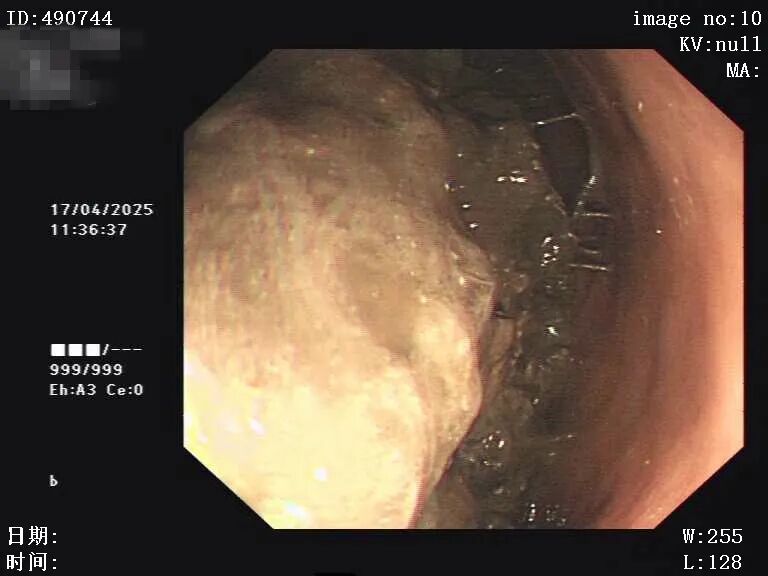

图片

4月26日胃镜检查:胃潴留